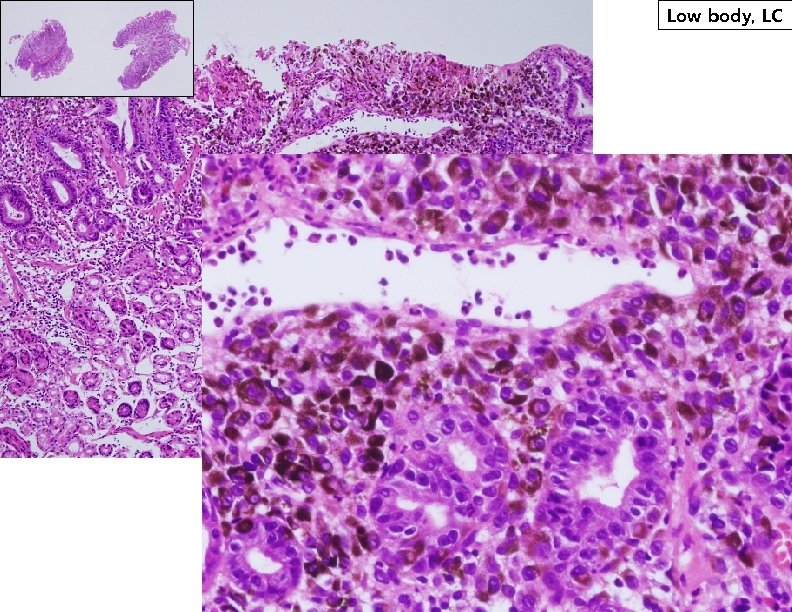

Low body, LC Low body, LC

S 100 HMB 45 Malignant neoplasm producing melanin pigments suggestive of Malignant Melanoma S 100 HMB 45 Malignant neoplasm producing melanin pigments suggestive of Malignant Melanoma